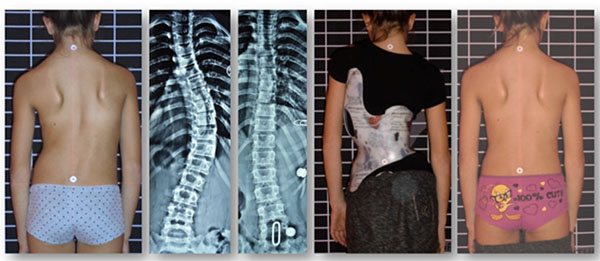

يعاني بعض الأطفال والمراهقين من اعوجاج العمود الفقري، وتتساءل الأسر كثيرًا: هل يمكن أن يؤثر اعوجاج العمود الفقري على شكل الوجه أو ملامحه؟ هل هناك تغييرات ظاهرية تستدعي القلق؟ وهل يمكن التدخل مبكرًا لتجنب أي تأثير؟ هذه الأسئلة شائعة، وتعكس نية البحث الحقيقية للأهالي الذين يريدون معلومات واضحة وبسيطة لفهم تأثير اعوجاج العمود الفقري على الجسم بأكمله، بما في ذلك الوجه.

التزام الطفل بالعلاج: عدم استخدام حزام اعوجاج العمود الفقري أو عدم ممارسة التمارين العلاجية قد يزيد اختلال التوازن ويزيد تأثيره على الرأس والوجه.

متابعة الزوايا والانحناءات باستخدام الأشعة عند الحاجة.

وفق توصية الطبيب، خصوصًا عند الانحناءات المتوسطة إلى الشديدة.

يساعد على تقويم العمود الفقري ومنع تفاقم الانحناء الذي قد يؤثر على الرأس.